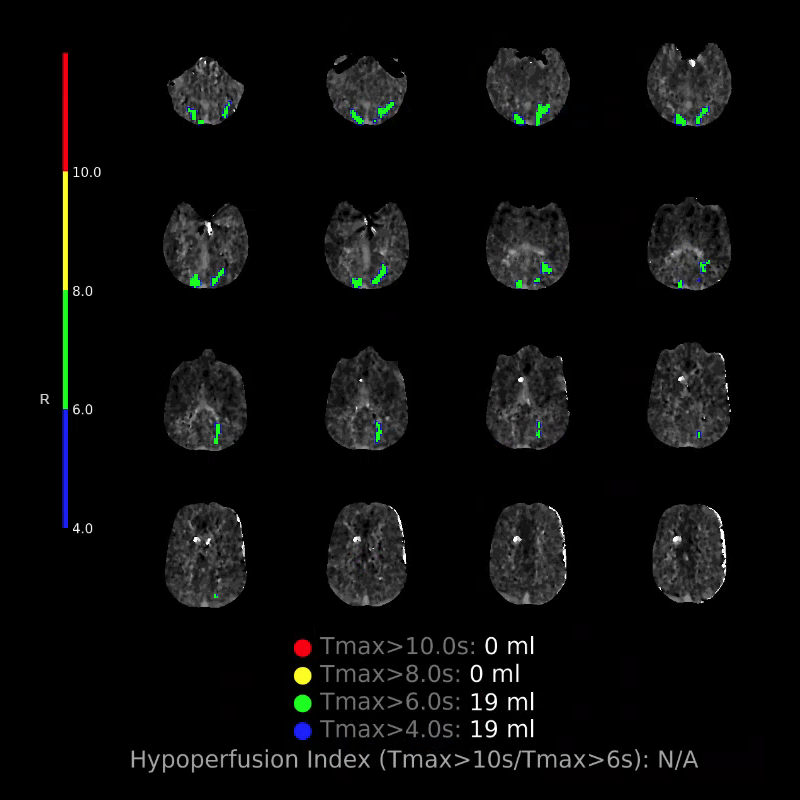

CTP

Starting with the non-contrast head CT, we can appreciate that there's actually not much residual subarachnoid blood at all; it's essentially all resorbed already (and cleared through the EVD). The ventricular caliber is stable. With the CTA head (for convenience's sake, the MIPs were shown), it's subtle, but we can see that the PCAs on each side are not as smooth and regular. The right MCA, starting at the bifurcation, also becomes narrower. This is [radiographic] vasospasm. Now, looking at the CT perfusion-- specifically, the Tmax (MTT) map that were selected-- there's clearly some abnormality within the bilateral cerebellar hemispheres and occipital lobes. Not a lot, but it's there. Delving further into this map, we can appreciate that the areas of abnormality are mainly green, signifying that these areas have Tmax > 6 seconds. This is the threshold that is specific, not sensitive, for vasospasm.

Putting this all together, we have thus identified radiographic vasospasm with the vessel imaging, with perfusion abnormalities that are concordant with it. Does the area of vasospasm and hypoperfusion correlate with the patient's clinical exam?

Yes! It does. The patient had a decline in level of consciousness with diffuse loss of motor function. This does correlate to the basilar territory. (Alternatively, bilateral MCA vasospasm could also be responsible, reminding us that a decline in consciousness could technically be focal/multifocal.) Thus, we can say that this patient does have clinical vasospasm. Whether this will develop into irreversible DCI remains to be seen; at least, the non-contrast head CT and the other portions of the CT perfusion (not shown) currently don't [yet] suggest infarction.